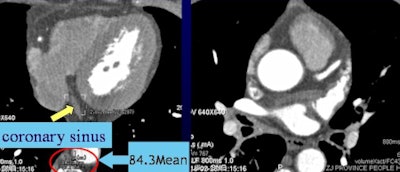

The study team measured attenuation at regions of interest in the ascending and descending aorta, left and right coronary arteries, and coronary sinus.

CT values in the coronary sinus were 112.7, 93.7, and 81.2 HU for Groups A, B, and C, respectively (p < 0.001). CT values within the ascending and descending aorta and the coronary arteries were higher than 300 HU in all three contrast groups.